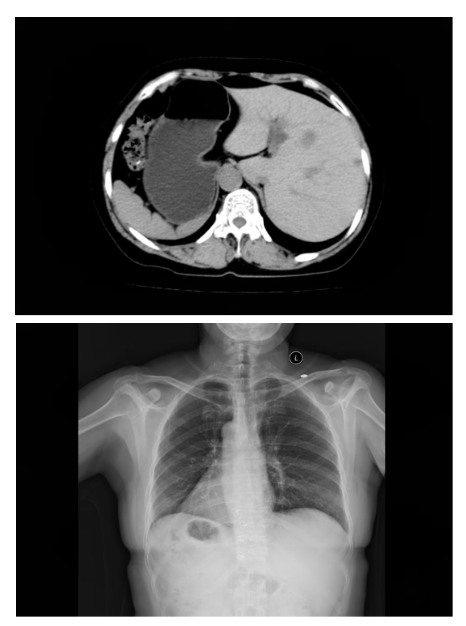

全内脏反位

什么是“全内脏反位”?简单来说,张女士的心脏、肝脏、胆囊、脾胃等所有胸腹腔器官,位置都与正常人完全左右对调。就像照镜子时看到的自己,医学上形象地称之为“镜面人”。

这种先天变异的发生率极低,大约每万人中仅有1例。对于普通人来说,这只是一个有趣的医学名词;但对于即将接受手术的张女士和她的主刀医生来说,这意味着巨大的挑战。